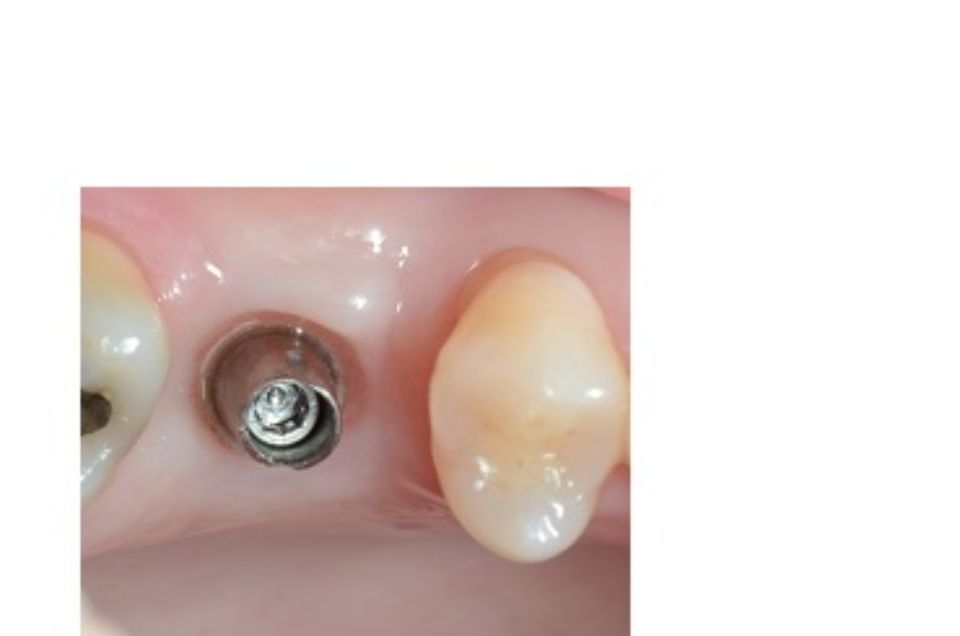

Implantologia bucal

La implantologia és l´especialitat odontològica que s´ocupa de la substitució de l´arrel de la dent perduda.

La substitució es fa mitjançant una petita intervenció quirúrgica per col·locar una peça de titani dins de l'os maxil·lar.

L'implant té una rosca al seu interior on posteriorment s'enroscarà el pilar que suportarà la corona protètica.

Després de la valoració de l'implantòleg i un diagnòstic molt acurat per part de l'equip professional, es plantegen diferents solucions. Depenent del problema plantejat que pot ser: pèrdua unitària, pèrdua múltiple o desdentat complet...es realitzarà la tècnica precisa per tal de millorar la qualitat de vida del pacient.